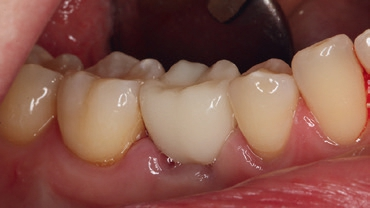

Eine 36-jährige Patientin stellte sich mir mit einem gefüllten Milchzahn an Position 85 vor. Der Zahn war aufgrund einer Sekundärkaries mit folglicher Pulpanekrose nicht erhaltungswürdig und sollte aufgrund der Nichtanlage des Zahnes 45 durch ein Implantat ersetzt werden (Abb. 1a und b). Zielsetzung war eine Sofortimplantation sowie die Sofortversorgung des Implantats. Eine andere Möglichkeit wäre eine kieferorthopädische Behandlung zum teilweisen oder vollständigen Lückenschluss gewesen oder alternativ die klassische Versorgung mittels einer 3-gliedrigen Brücke, jedoch bei unversehrten Pfeilerzähnen. Beide Konzepte schieden patientenseitig aus.

Die intraorale Röntgenaufnahme zeigte die übliche 2-wurzelige Konfiguration des Milchmolaren, apikal das Foramen mentale sowie gering ausgeprägte trabekuläre Strukturen der regionalen Spongiosa aufgrund der kurzen Wurzelkonfiguration (Abb. 2). Eine geführte Implantation, für deren Umsetzung ein DVT angefertigt wurde (Orthophos XG 3D), bot hier den Vorteil einer sicheren Führung ohne Richtungsablenkung durch die bestehenden Alveolen sowie der optimalen Ausnutzung des vorhandenen Raumangebots, um maximale Stabilität zu erreichen. Aufgrund der größeren mesiodistalen Breite des Zahnes 85 im Vergleich zu üblichen Prämolaren orientierte ich mich bei der prothetischen Planung am vorhandenen Milchmolaren.